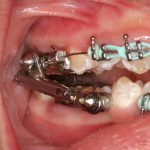

De ADVANCE is een vaste beugel, die aan je kiezen bevestigd wordt. Hij wordt ook wel het ADVANCE-scharnier genoemd. Hij bestaat uit twee gedeelten. Elk gedeelte bestaat uit een metalen kroontje, met daaraan vast een scharnier. Op de scharnieren zijn een buisje en een staafje bevestigd, die in elkaar schuiven.

Doordat het buisje en het staafje iets te lang zijn, wordt je onderkaak naar voren gedwongen. De groei van de bovenkaak wordt verminderd, terwijl de onderkaak sneller gaat groeien.